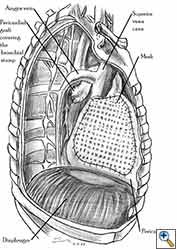

Medium and large-sized (Figures 1a, 1b) defects generally result after pneumonectomy for advanced central lung tumours which invade the pericardium (T3 invading pericardium), thus requiring reconstruction (Figure 1c). To achieve a curative resection, negative pericardial resection margins must be obtained and checked microscopically. More invasive tumours (T4 invading cardiac structures) require partial atrial resection and pericardiectomy associated with pneumonectomy.

|

| Figure 1c: Intraoperative aspect of pericardioplasty with Marlex mesh after right completion pneumonectomy with partial pericardiectomy. |

Video 1 depicts a pericardial reconstruction with Marlex after a right completion pneumonectomy with pericardiectomy for lung adenocarcinoma (see also Figure 1). The technique of pericardial reconstruction after the resection of invasive mediastinal tumours is illustrated in Figures 8a-c). Video 2 depicts a pericardial reconstruction with Mersilene mesh after the resection of a malignant thymoma invading the anterior pericardium (see also Figure 4b). The technique of right pericardial reconstruction after extrapleural pneumonectomy is illustrated in Figures 9a and 9b). Video 3 depicts a pericardial reconstruction using Gore-Tex Dual Mesh after a left extrapleural pneumonectomy (see also Figure 3). Care must be taken to prevent constriction (Figure 10).